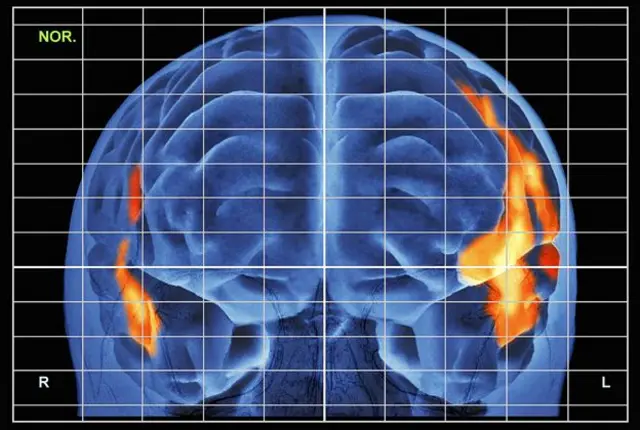

Es más, un análisis de nuestros patrones cerebrales durante el ejercicio reveló algo aún más sorprendente.

Mientras que yo usé todas mis armas mentales, iluminando mi monitor cerebral como si fuese un cielo cubierto por fuegos artificiales, el monitor de Tokiko mostró que estaba usando sólo una parte mínima de sus facultades.

Kawashima me explicó que mi oponente no sólo me había ganado, sino que lo había hecho con un brazo atado a la espalda.

La anciana había usado una fracción de su poder mental, mientras que yo había puesto todo mi arsenal en funcionamiento.

Este desempeño brillante, dijo, fue el resultado de un entrenamiento de 15 minutos al día.